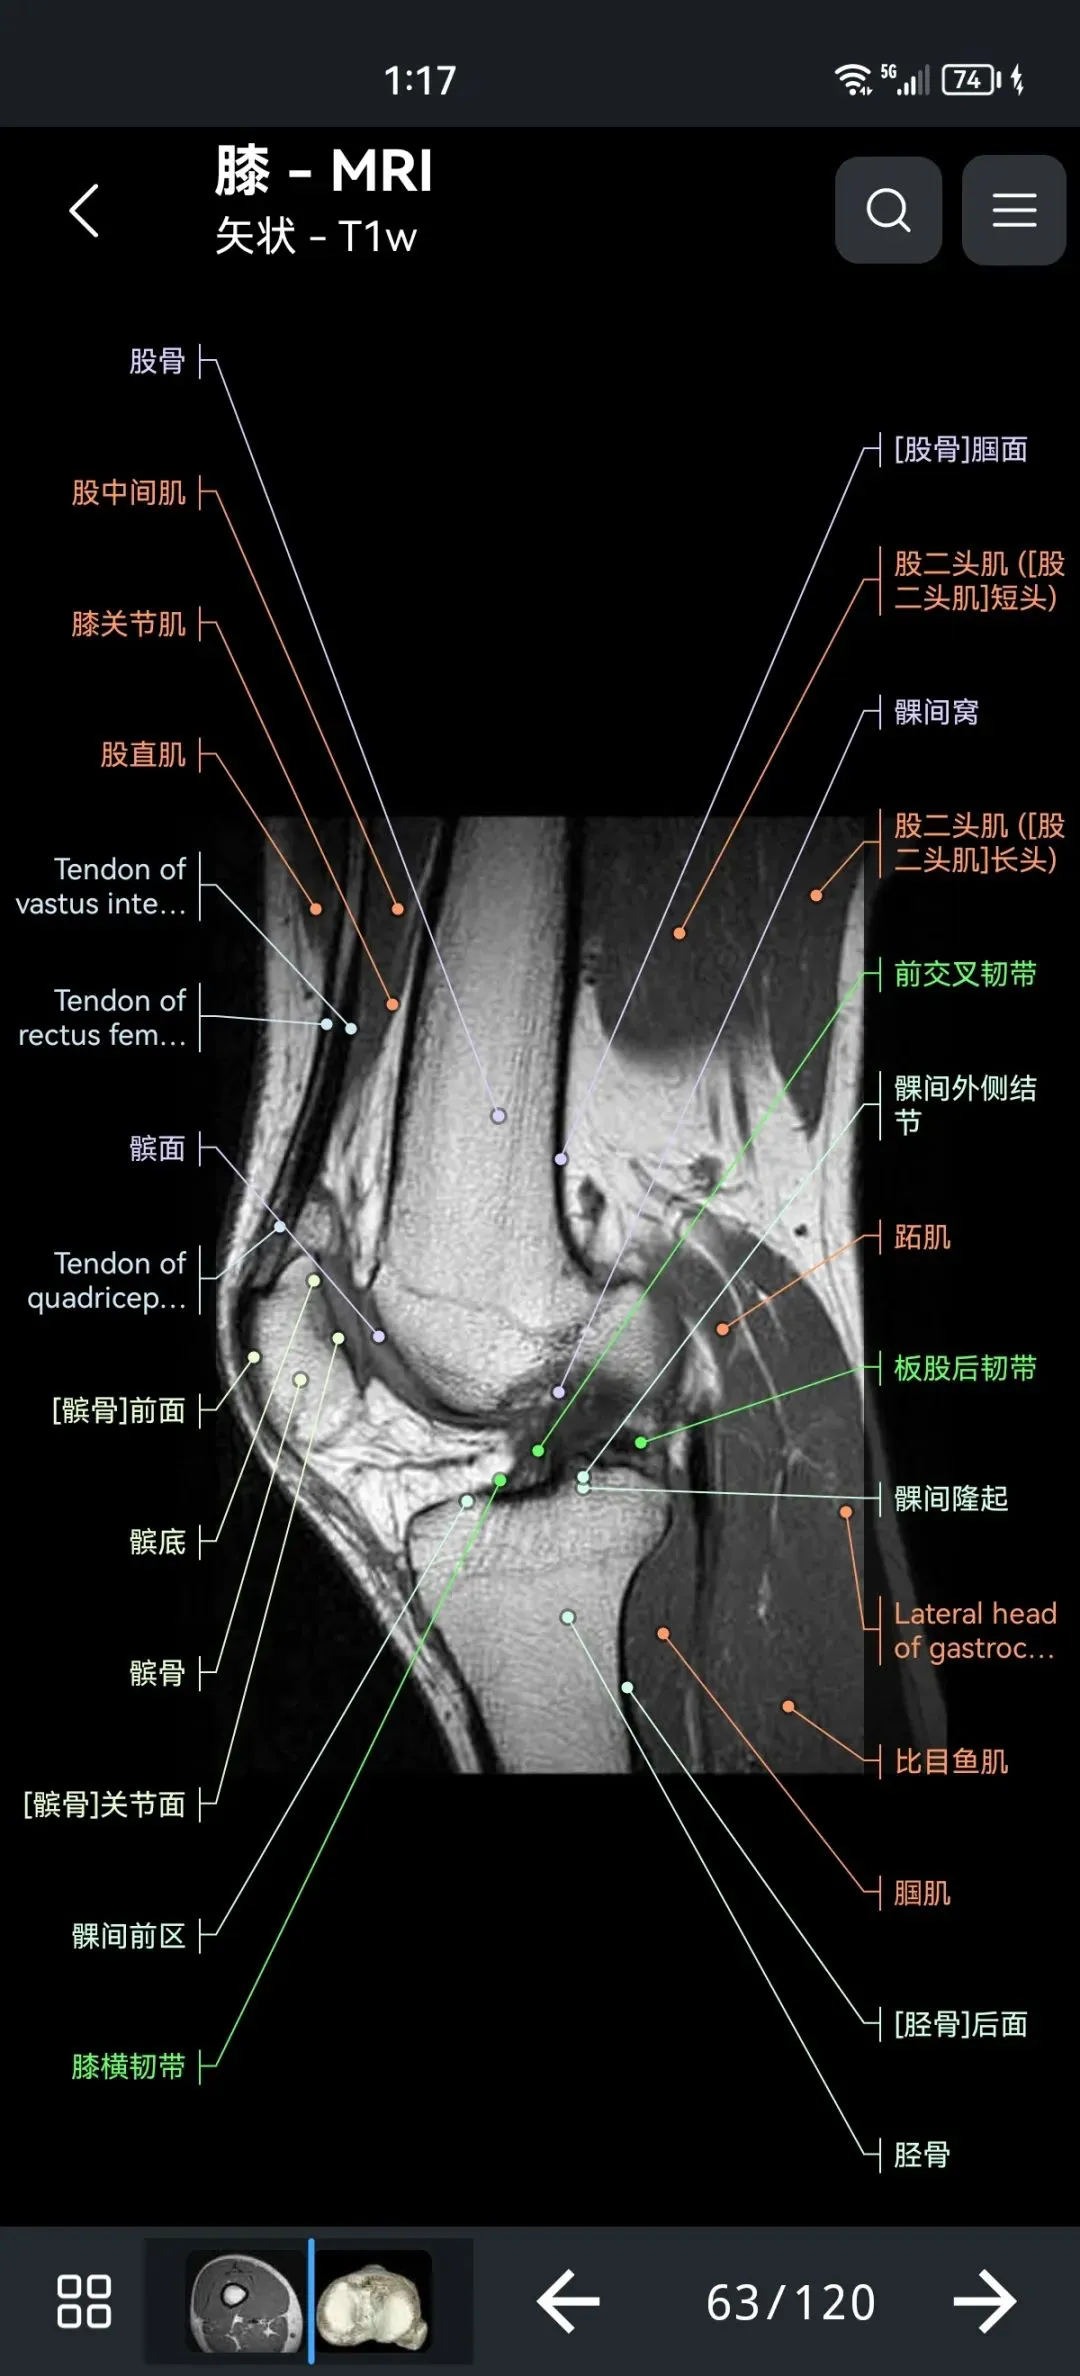

🌈这是国外引进的一款专业影像解剖学习软件。

覆盖了X光、CT、MRI、断层大体解剖、核医学、介入造影、医学插图等多个模块,覆盖全身各个系统的影像解剖(正常解剖结构,无病例),其中的解剖结构高达87万个,结构标注超精细,超高清图像,历时两年研发设计完成✅。